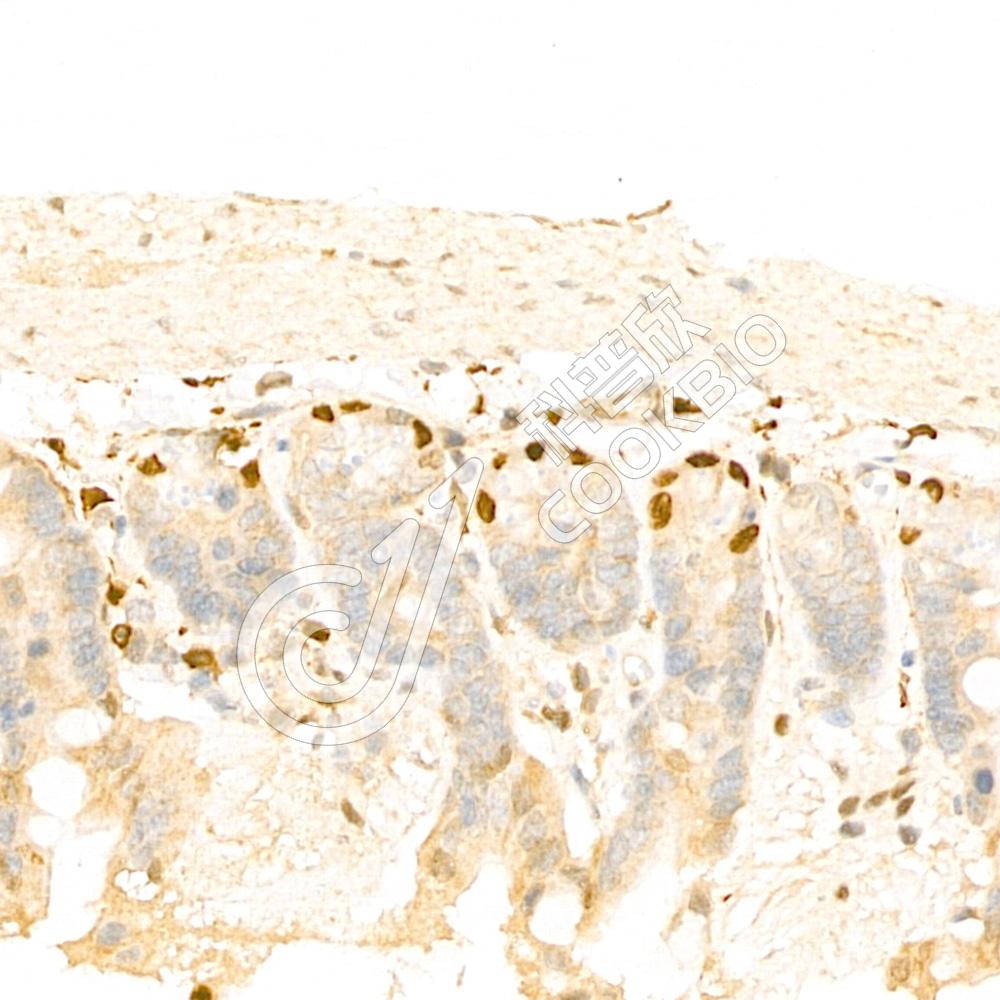

IF检测GSK3 beta蛋白(货号 K133297)(红色).

样品: 小鼠睾丸, 4%多聚甲醛 (货号KSG1101) 固定12-24小时.

抗原修复: Tris-EDTA抗原修复液(pH 9.0) (KSG1203), 98℃, 20分钟.

封闭: 3% BSA(货号KSGC305010)的PBS溶液, 室温孵育30分钟.

—抗: 1: 600稀释, 4℃ 孵育过夜.

二抗: Cy3标记山羊抗兔IgG (H+L) (货号KB63909), 1: 300稀释, 室温孵育1小时.